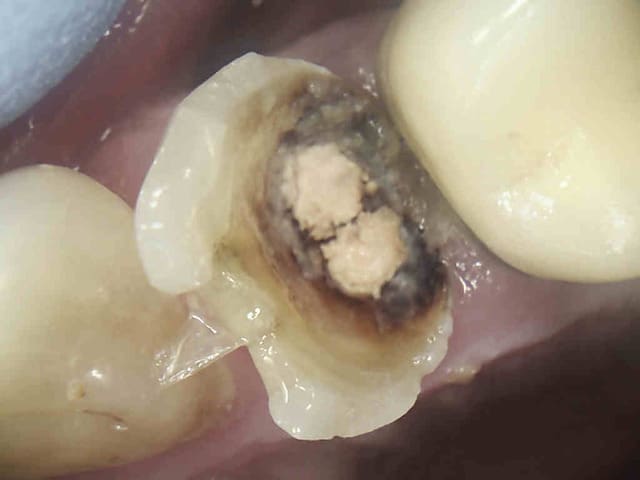

J'ai un de mes patients du cabinet où je travaillais avant qui m'a contacté car il a une reprise d'infection sous la CCM sur 46. Le praticien lui a déposé la couronne et va entreprendre le retraitement endodontique. Puis réaliser une nouvelle couronne. Etant donné que cela fait 3 ans que la couronne est posée le patient est mécontent. Il m'a appelé pour savoir s'il était possible d'avoir une indemnisation.

Je vous mets les photos en pièce jointe.

Ton endo était pas mal.

C'est étonnant que le matériau d'obturation qui était dense en 2011 se soit dégradé à ce point et si vite.

Il est possible qu'il y ait autre chose (perfo latérale un peu en dessous du plancher, fracture de la racine MV).

Pour moi jusqu'à preuve du contraire c'est un alea.

Oh la belle peinture...

Par contre à ta place je ne contesterais rien du tout, t'es en tort à 300%. J'espère pour toi que toutes tes endos ne sont pas comme ça. Certains me diront que je suis sévère blablabla "ça t'es jamais arrivé de rater" etc, mais en sortant de la fac faire ça je trouve ça honteux.

Mets au moins un cône un minimum calibré. La gutta ne "disparaît" pas.

il peut la reprendre comme il veut l'endo , elle parait cuite la dent. ça a l'air multifactoriel ce truc avec une tres tres grosse composante occlusale .

Completement d'accord avec enlaye pour le multifactoriel ;l'infection est inter radiculaire , suite a une recession parodontale importante ,il suffit de voir la radio. Le retraitement (avec ou sans digue, :-)) est bien, mais ne donnera rien de plus!

Pour l'endo, c'est vrai que la disparition du matériaux d'obturation ne plaide pas en la faveur de notre jeune confrère.

La radio post-op du 15/11/2011 semble montrer la présence de cône de gutta dépassant coronairement . L'erreur ne viendrait-elle pas d'une empreinte de l'ic dans la foulée .

la préparation a retiré les cônes laissant le ciment endodontique.

Concernant une lésion interradiculaire je suis dubitatif en voyant uniquement cette radio .